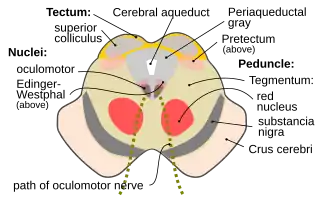

Поперечное сечение среднего мозга на уровне четверохолмия (точнее Superior colliculus). Отчётливо видны красные ядра (nuclei rubri), ядро глазодвигательного нерва (nucleus nervus oculomotorius), водопровод мозга (aqueductus cerebri) и околоводопроводная область, пунктиром отмечен путь глазодвигательного нерва (nervus oculomotorius). | |

Чёрная субстанция, также чёрное вещество (лат. Substantia nigra) — составная часть экстрапирамидной системы[1], находящаяся в области четверохолмия среднего мозга. Играет важную роль в регуляции моторной функции, тонуса мышц, осуществлении статокинетической функции участием во многих вегетативных функциях: дыхании, сердечной деятельности, тонусе кровеносных сосудов[2]. Впервые обнаружена французским анатомом и врачом Феликсом Вик-д'Азиром в 1784 году[3].

Представляет собой скопление нервных клеток. Расположена в дорсальной части ножки на границе с базальной частью среднего мозга. Substantia nigra простирается на всём протяжении ножки мозга от моста до промежуточного мозга. Люди имеют две Substantiae nigrae, по одной на каждую сторону (левую и правую), от средней линии мозга.